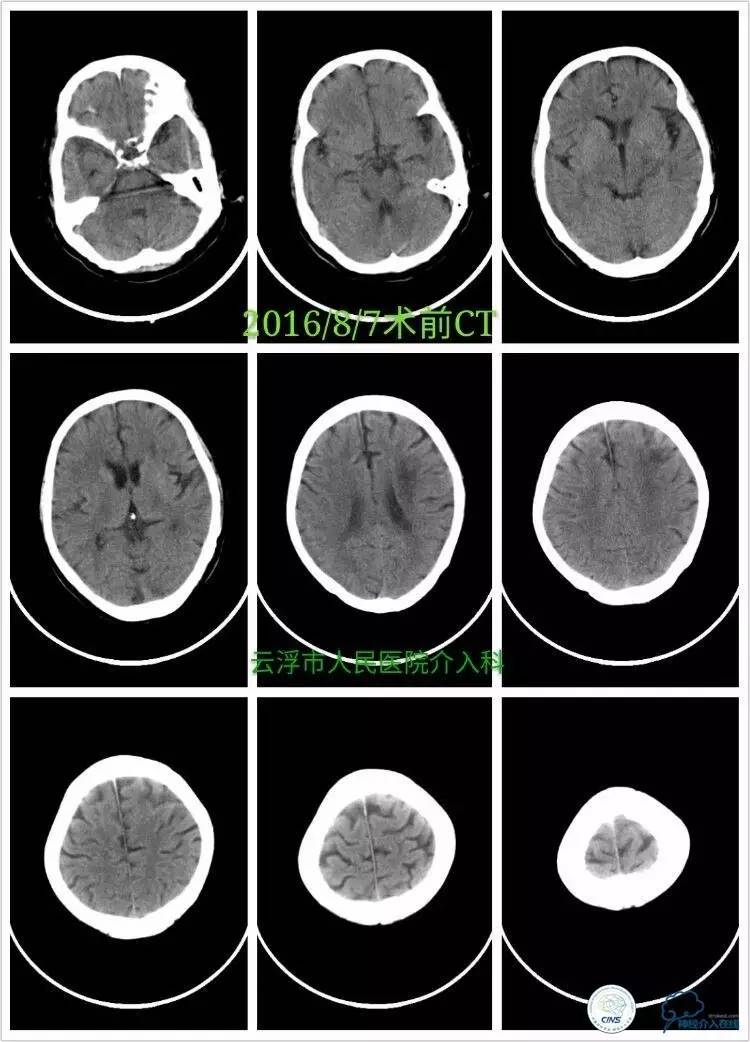

》术前颅脑CT平扫:

》2016-08-08

行左侧颈内交通段、左椎开口支架成形术治疗。